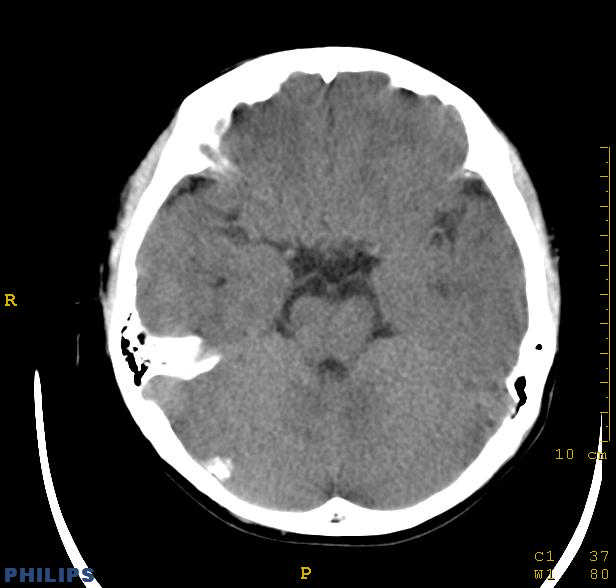

标题: PED0043:头颅平扫 男12岁.典型结节性硬化 [打印本页]

标题: PED0043:头颅平扫 男12岁.典型结节性硬化

典型结节性硬化

[病因病理]

结节硬化是常染色体显性遗传缺陷或基因突变引起的疾病,脑部病理可见神经胶质增生性硬化结节,位于大脑皮质、基底核及侧脑室壁的室管膜下。结节质地较硬,多有钙化。室管膜下结节可演变为巨细胞星形细胞瘤,亦可发生皮质错构瘤,常合并有其他器官畸形和肿瘤。

[影像学表现]

1.ct表现:

①室管膜下有多发性小结节状钙化影,也可为单发、不强化;小结节亦可未钙化;突入脑室可以强化;但有钙化者居多,颅内异常钙化高达90%。一般出生后2年即呈典型钙化。

②10%-15%的病例可能恶变为室管膜下巨细胞星形细胞瘤或其他胶质瘤。前者常位于室间孔附近,生长缓慢,增强扫描可产生异常强化。

③可见白质区脱髓鞘的低密度区。

④可伴脑灰质异位。

⑤脑室扩大系阻塞性脑积水或脑发育不良所致。